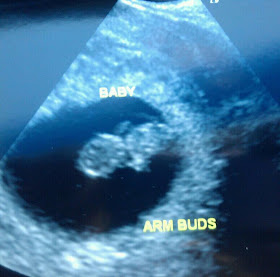

1st Photo

How far along? 8 weeks + 6 days {9/7/11}

Best moment this week: getting the 1st photo of baby and hearing the heartbeat :)

12 weeks

Best moment this week: seeing the baby's heartbeat and getting another photo :)

13 weeks + 3 days {10/9/11}

How far along? 13 WEEKS + 3 DAYS {10/9/11}

Best moment this week: hearing heartbeat {ER} and seeing baby and heartbeat {ER}